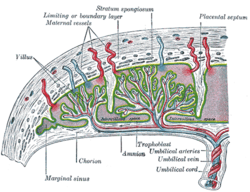

Structure

In humans, the placenta averages 22 cm (9 inch) in length and 2–2.5 cm (0.8–1 inch) in thickness, with the center being the thickest, and the edges being the thinnest. It typically weighs approximately 500 grams (just over 1 lb). It has a dark reddish-blue or crimson color. It connects to the fetus by an umbilical cord of approximately 55–60 cm (22–24 inch) in length, which contains two umbilical arteries and one umbilical vein.[5] The umbilical cord inserts into the chorionic plate (has an eccentric attachment). Vessels branch out over the surface of the placenta and further divide to form a network covered by a thin layer of cells. This results in the formation of villous tree structures. On the maternal side, these villous tree structures are grouped into lobules called cotyledons. In humans, the placenta usually has a disc shape, but size varies vastly between different mammalian species.[6]

Placental circulation

Maternal placental circulation

In preparation for implantation of the blastocyst, the uterine endometrium undergoes "decidualisation". Spiral arteries in decidua are remodeled so that they become less convoluted and their diameter is increased. The increased diameter and straighter flow path both act to increase maternal blood flow to the placenta. The relatively high pressure as the maternal blood fills intervillous space through these spiral arteries bathes the fetal villi in blood, allowing an exchange of gases to take place. In humans and other hemochorial placentals, the maternal blood comes into direct contact with the fetal chorion, though no fluid is exchanged. As the pressure decreases between pulses, the deoxygenated blood flows back through the endometrial veins.

Fetoplacental circulation

Deoxygenated fetal blood passes through umbilical arteries to the placenta. At the junction of umbilical cord and placenta, the umbilical arteries branch radially to form chorionic arteries. Chorionic arteries, in turn, branch into cotyledon arteries. In the villi, these vessels eventually branch to form an extensive arterio-capillary-venous system, bringing the fetal blood extremely close to the maternal blood; but no intermingling of fetal and maternal blood occurs ("placental barrier").[9]

Placenta held. Schematic view of the placenta

Schematic view of the placenta- Maternal side of a whole human placenta, just after birth